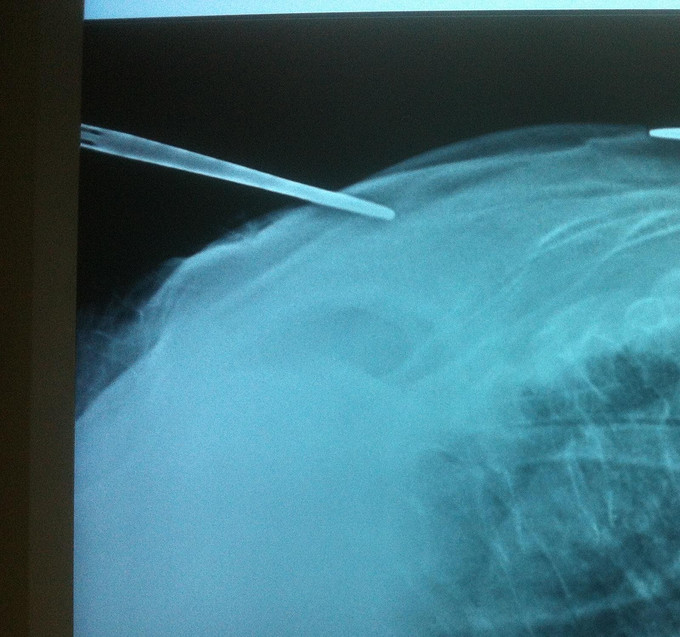

诊断:胸椎骨折 骨质疏松症 处理: 1、完善相关辅助检查,明确诊断,有无手术指证; 2、完善手术评估,有无手术禁忌,手术风险及并发症; 3、在局麻下行胸椎骨折椎体pkp术 4、术后给予全身抗骨质疏松治疗